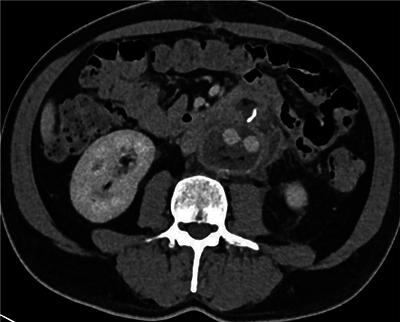

Aortoenteric Fistula with Digestive Contrast Material Leaking in the Aneurysmal Sac.

Teaching point: Aortoenteric fistula, a major complication of aortic surgery, can be identified with certainty on CT scan with opacification of the intestinal tract.